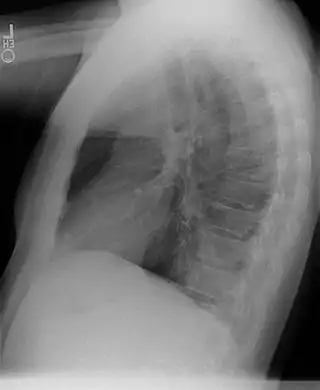

Secuestro broncopulmonar

Un secuestro broncopulmonar es una anormalidad congénita de una porción del pulmón que está separada del resto del parénquima pulmonar, recibiendo su aporte sanguíneo de una arteria sistémica.

Generalmente diagnosticada en niños. El tratamiento es la segmentectomía a través de una toracotomía. Son más frecuente en el pulmón izquierdo y en los lóbulos inferiores (60%-90%), aunque pueden verse en cualquier lóbulo, incluir todo el pulmón o incluso debajo del diafragma simulando un tumor abdominal.